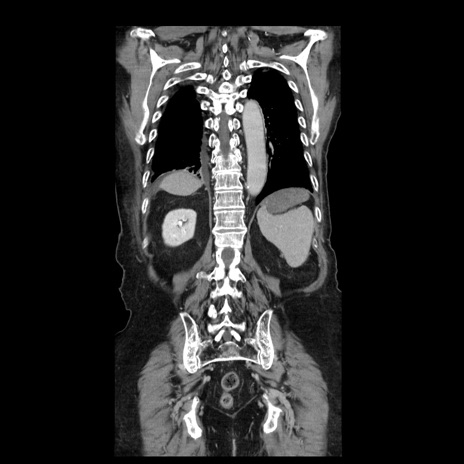

横断像

【症例】70歳代男性

【主訴】腹痛

【現病歴】肝硬変・肝細胞癌にてかかりつけの方。約9時間前に食後より腹痛出現。症状が徐々に増悪し、嘔吐出現したため来院。

【既往歴】肝硬変、肝細胞癌(RFA、TACE後)

【身体所見】意識清明、表情苦悶様、BT 36℃、BP 129/78mmHg、P 88bpm、SpO2 97%(RA)、右上腹部から心窩部にかけて圧痛あり、反跳痛なし、筋性防御あり。

【データ】WBC 5800、CRP 0.16